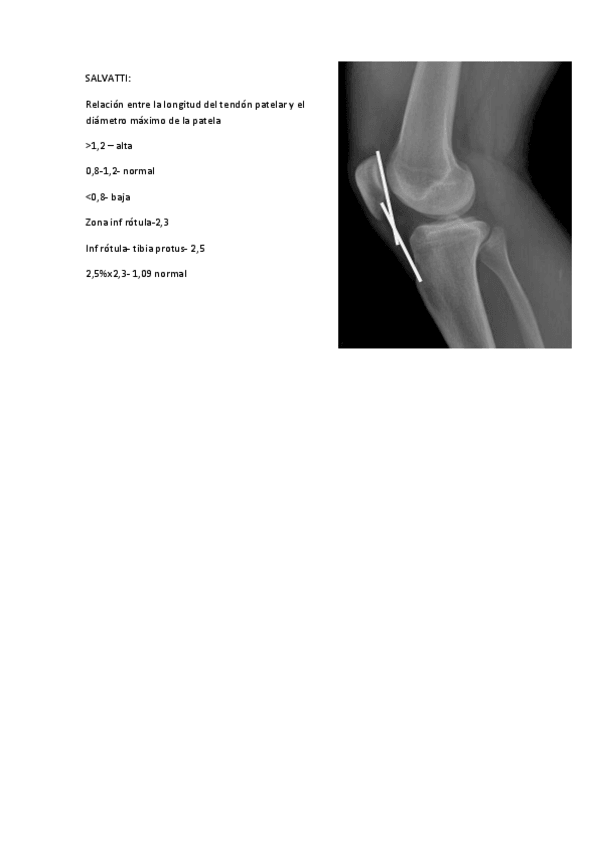

He publicado nuevos ejercicios de 3º Podología Deportiva: IMAGENES-PARA-GONIOMETRIA-DE-LA-RODILLA.pdf